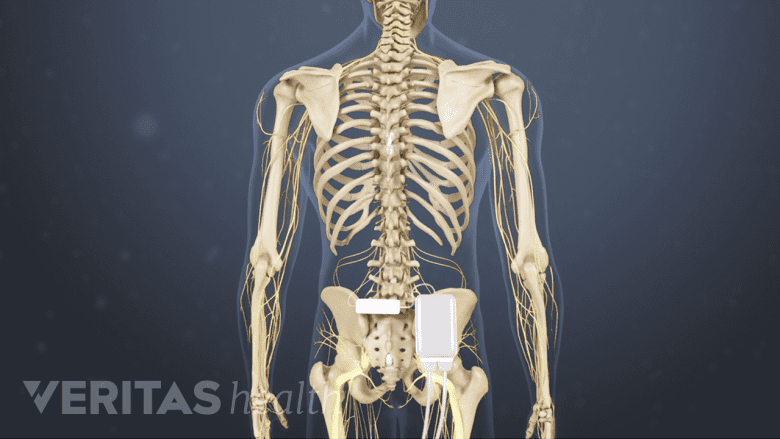

Spinal Cord Stimulation (SCS): Reducing Pain Through Electric Stimulation

SCS delivers mild electrical pulses to the nerves in the spinal cord.

Spinal cord stimulation, also called neurostimulation, is a treatment where mild electrical pulses are directed to the nerves in the spinal cord. These impulses interfere with pain signals, stopping them from reaching the brain.

Spinal cord stimulation surgery includes the implantation of a small device (similar to a cardiac pacemaker) near the spine, which generates these pulses. One benefit of this procedure is that it is tried for a short time before a person commits to having the surgical implant.